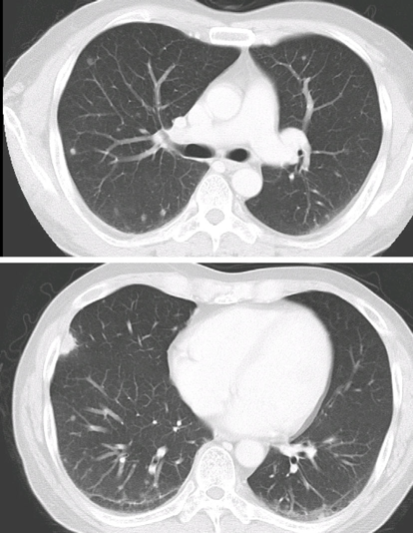

图6 25岁男性,因咯血急诊,3天前诊断水痘,被其3岁女儿传染,CT示两肺多发性边缘模糊的小叶中央型结节与伴外周GGO的微结节,以上叶为主。(Médart, L, et al. Varicella Pneumonia.)

介绍一个有免疫抑制的水痘案例:43岁日本男性,有恶性淋巴瘤史,予C-MOPP方案化疗,因皮疹入院,无呼吸道症状,诊断为水痘,予无环鸟苷+免疫球蛋白治疗。肺部CT示两肺多发性结节(图7、8)。

图7 CT示两肺多发结节(Isobe T, et al. Intern Med. 2019)